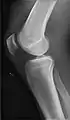

• Knee - AP and Lateral. Intra Condular projections on request

• Patella - Skyline projection

Certain suspected conditions require specific projections. For example, skeletal signs of rickets are seen predominantly at sites of rapid growth, including the proximal humerus, distal radius, distal femur and both the proximal and the distal tibia. Therefore, a skeletal survey for rickets can be accomplished with anteroposterior radiographs of the knees, wrists, and ankles.[20]